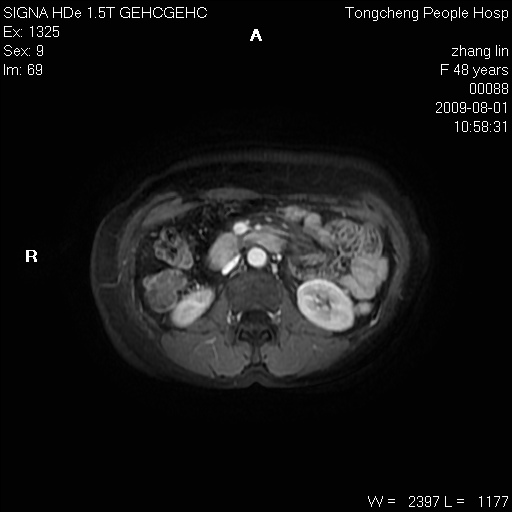

女,48岁。健康体检,彩超发现右肾占位性病变。平素健康。

临床诊断:右肾占位性病变,性质待定(囊肿?肿瘤?)。

上中腹部mr平扫+增强扫描,图像如下:

右肾上极见一类圆形病灶,t1wi呈等信号t2wi呈等高混杂信号,三期增强无强化,边界清---考虑囊肿出血。

同反相位均表现为等信号,病变无强化,考虑含蛋白的囊肿可能,弥散加权相或许有些帮助,

慢性胆囊炎